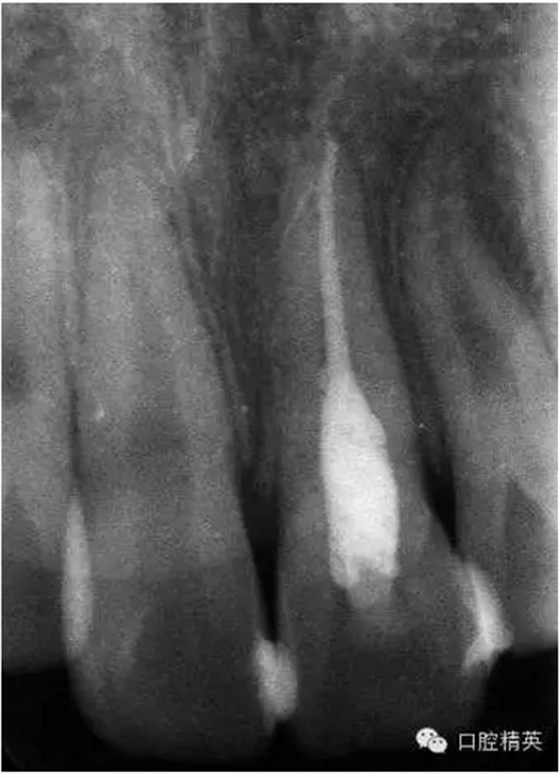

x線檢查:21牙槽窩空虛,窩內(nèi)未見(jiàn)其他遺留物。

圖3.患者21根尖片,牙槽窩空虛,無(wú)變形。

圖18.復(fù)位臨時(shí)固定后的x線根尖片?;颊哐栏c牙槽窩吻合。

圖23.樹(shù)脂+牙弓夾板固定完成后的x線片影像

圖5.拆除樹(shù)脂夾板前的x線根尖片影像,21根尖出現(xiàn)少許吸收。大家擔(dān)心的情況出現(xiàn)了。